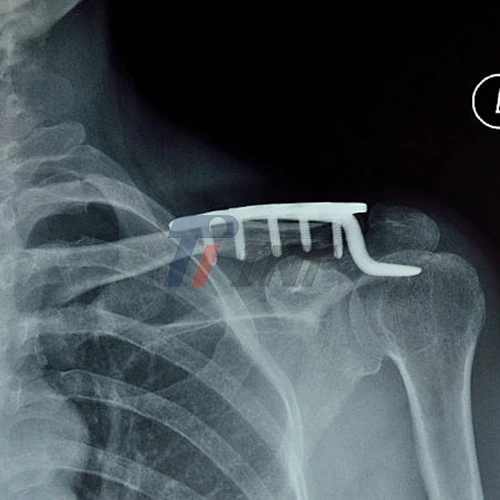

The healing process following clavicle surgery with a titanium plate demands significant energy and nutrients. A well-balanced diet accelerates recovery, reduces complications, and promotes optimal bone healing. The clavicle surgery titanium plate provides stability, but your body needs proper nutrition to form new bone tissue and repair damaged soft tissues.

Proper nutrition is a crucial component of recovery after clavicle surgery with a titanium plate. By focusing on nutrient-rich foods, maintaining adequate hydration, and considering appropriate supplements, you can support optimal healing and recovery. Remember, the clavicle surgery titanium plate provides stability, but your body's natural healing processes, supported by proper nutrition, are what ultimately lead to full recovery.